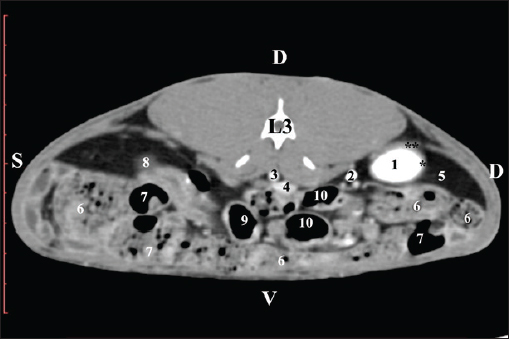

Fig. 7. Pre-contrast computed tomography (CT) anatomical scan of the regio-abdominis media at the caudal L3 edge level. (1) Ren dexter; (2) adipose collection; (3) cecum; (4) colon ascendens; (5) colon transversum; (6) colon descendens; (7) mesenterium. The transverse pre-contrast examination of the regio abdominis media at the L3 level (through the cranial part of the vertebra) revealed the left kidney’s extremitas cranialis as an oval soft tissue with normoattenuated soft tissue characteristics. Ventrally, the kidney was adjacent to the duodenal pars ascendens, ileum, colon ascendens, and colon descendens. Hypoattenuated abdominal adipose collections were observed around it (Figs. 8 and 9).

Fig. 8. Pre-contrast computed tomography (CT) anatomical scan of the regio-abdominis media at the cranial L3 edge level. (1) Ren sinister; (2) adipose collections; (3) cecum; (4) colon ascendens; (5) jejunum; (6) pars ascendens of the duodenum; (7) colon descendens; (8) colon transversum; (9) colon descendens.

Fig. 9. Pre-contrast computed tomography (CT) anatomical scan of the regio-abdominis media at the caudal L3 edge level. (1) Ren dexter; (2) adipose collections; (3) cecum; (4) colon ascendens; (5) jejunum; (6) pars ascendens of the duodenum; (7) colon descendens. The pre-contrast anatomical scan at the L4 level provided data about the location of the renal pelvis within the renal sinus. The initial part of the pelvis renalis appeared as a distinct funnel-shaped hypoattenuated soft tissue, whose central part was widened and formed the recessus renalis. The transition of the narrowed end of the renal pelvis into the hypoattenuated left ureter was without a sharp boundary. The left kidney was in contact with the cecum, colon ascendens, and colon transversum ventrally. Crista renalis was observed as a hypoattenuated linear soft tissue finding (Figs. 10 and 11).